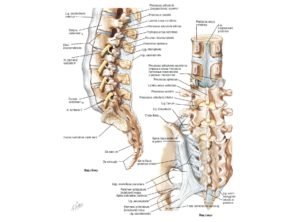

От тела позвонка назад идёт дуга, замыкающая позвоночное отверстие и переходящая далее в остистый отросток. На плоскости дуги в обе стороны расположены поперечные отростки, которые являются рудиментами рёбер. У основания поперечных отростков поясничных позвонков заметен рудимент истинных поперечных отростков (processus accessorius), который при большой длине (4 мм) приобретает форму шила (processus styloideus). Авторы М. Г. Привес, Н. К. Лысенков, В. И. Бушкович замечают, что его не следует принимать за патологическое образование. На верхней и нижней гранях дуги расположены парные верхние и нижние суставные отростки. В четырёх верхних поясничных позвонках остистые отростки направлены прямо назад, суставные расположены сагиттально. Позвоночные отверстия, начиная со второго поясничного позвонка, постепенно сужаются, что связано с анатомией спинного мозга.

Тело пятого поясничного позвонка в направлении к остистому отростку имеет клиновидную форму, при этом оно наклонено вперед, так как крестцовая кость направлена назад, формируя кифоз. Суставные отростки размещены в полуфронтальной, полусагиттальной плоскостях.

Центральная ось скелета, позвоночник, формируется 24 позвонками, крестцом и копчиком. Он содержит спинной мозг и спинномозговые нервы. Он связан с тремя блоками: головой, грудной клеткой и тазом, и содержит зоны, которые образуют три последовательных изгиба, видимых в профиль.

Очень сочлененный, он содержит 74 сустава, в т.ч. 23 межпозвоночных диска. Он может поочередно становиться несущей колонной для корпуса, жесткой и прочной, или гибкой и подвижной связью благодаря многочисленным мышцам, которые могут его зафиксировать или заставить двигаться.